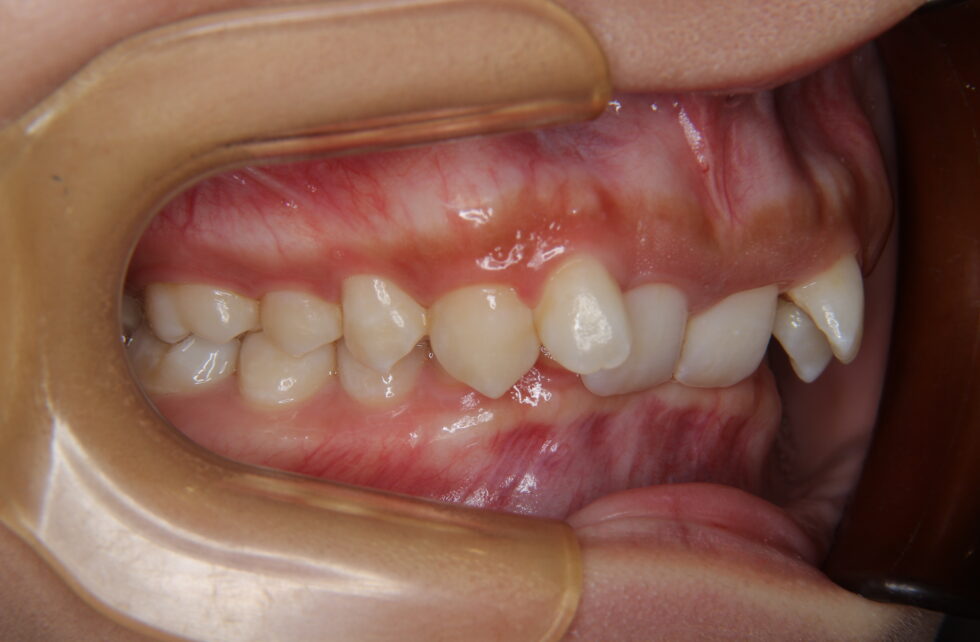

初診時年齢24歳の女性 上顎前歯の内傾を主訴にご来院いただいた。長年、前歯が内側を向いていることを気にされていたが治療を行う勇気が出なかったとのことであった。しかし、咬合時に上顎前歯に痛みを感じるようになったことから治療を希望された。セファログラム他の分析から咬合力の極めて強いと考えられる骨格をされていることが分かった。上あごの前歯が内側を向いた骨格性上顎前突で、アングルの分類Ⅱ級2類と診断した。咬合力が強いと歯の動きは緩徐で、前歯のかみ合わせが深くなり、上あごの前歯の後退が困難になる場合がある。このため、上顎左右側小臼歯を抜歯していただき、矯正用アンカープレートを併用して、上下顎マルチブラケット装置を使用して動的治療を行った。内側を向いていた上顎前歯は適正な角度とすることができた。